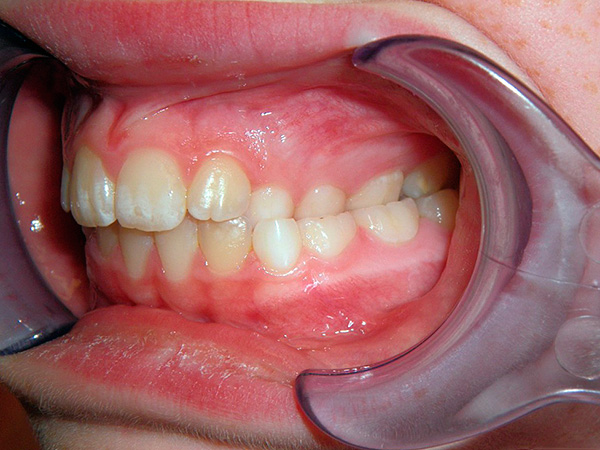

Uma mordida cruzada na região lateral também é diferenciada - a patologia é caracterizada pelo fechamento inadequado de pré-molares e molares (ou seja, 4, 5, 6 e 7 dentes, bem como dentes do siso). Como na região anterior, com uma mordida cruzada dos dentes posteriores, a anomalia pode afetar apenas um dente, vários ou mesmo todo o segmento lateral.

Ao diagnosticar uma mordida cruzada na seção lateral, é importante esclarecer em qual direção o maxilar inferior é deslocado e se há um deslocamento em apenas um lado da dentição ou em ambos. Dependendo disso, os ortodontistas distinguem uma mordida cruzada lateral unilateral e bilateral.

Por sua vez, uma mordida cruzada lateral unilateral pode se manifestar de diferentes maneiras, a saber:

- Mordida cruzada unilateral com deslocamento para a língua (mordida lingual). Esse tipo de mordida cruzada geralmente ocorre devido a aglomeração, como resultado da falta de espaço na arcada dentária. Ou em crianças com atraso na troca de dentes de leite na picada de leite;

- Mordida cruzada unilateral com deslocamento em direção à bochecha (mordida bucal). Esse tipo de anomalia é bastante raro, pode ser, por exemplo, devido à colocação inadequada das gemas dos dentes, o que faz com que os dentes entrem em erupção do lado de fora da dentição para o lado da bochecha. No entanto, quanto mais os dentes estiverem em um fechamento tão anormal, mais provável é que a causa desse tipo de mordida cruzada seja a assimetria do desenvolvimento da mandíbula;

- E, finalmente, uma mordida cruzada unilateral com uma mudança em direção ao palato (mordida palatinal). É diagnosticada quando um ou mais dentes do segmento lateral estão inclinados para o céu. As causas deste tipo de oclusão podem ser macrodentia (dentes excessivamente grandes) e a ausência de dentes individuais.Por via de regra, a patologia é mais comum em malformações congênitas ou lesões e doenças da articulação temporomandibular (ATM).